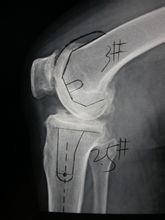

椎间盘、小关节、椎体形成一个三角形的支架结构,以稳定椎体间的关系,其功能是三位一体的。当椎间盘退行性变或椎体间关节受到损伤后,小关节的稳定性遭到破坏而出现病理性改变,关节囊变得松弛,导致关节突半脱位,形成损伤性关节炎。由于具备的变性,椎间关节间隙变窄和骨赘形成,椎间孔的前后径及椎体上下间隙变小,刺激和压迫脊神经和血管,影响局部血液循环和脊神经功能。由于脊柱呈垂直状排列,越是下位的椎体关节,负重越大,因此也越易受累,也最早发生退变。所以我们常常看到,颈椎4-7最容易发生病变。随着颈椎小关节的退行性变,小关节、钩椎关节以及其它结构的正常关系也发生改变:(1)椎间孔上下径变窄:由于椎间盘退化变窄,上下椎体接近,故椎间孔的上下径变窄。(2)椎间孔前后径变窄:由于颈椎的小关节面具有自前上向后下倾斜的解剖特点,故当椎间盘变性时,上面的椎体即沿着这个斜面向后滑而发生半脱位,造成椎间孔前后径变窄而压迫神经根,同时椎管前后径亦变窄而压迫脊髓,又由于椎间盘各部的变性程度不一,左右上下压缩变扁的情况不尽相同,可以出现椎体偏歪旋转,棘突也相应地表现出左右偏歪。椎管狭窄指椎管、神经根管及椎间孔狭窄所引起的神经根、脊神经等压迫综合征。大多因骨性椎管或硬脊膜囊狭窄引起,但不包括椎间盘突出以及感染、肿瘤等所致的椎管狭窄。退行性椎管狭窄阶段

1、椎管狭窄的分类:按照受累的部位,分为局限性和广泛性两种。局限性狭窄是指一个或一个节段的部分狭窄;广泛性狭窄指两个或两个以上节段的狭窄。局限性又可以分中央型、侧隐窝型及神经根型狭窄。按照病因可以分先天性及继发性两种。2、退行性椎管狭窄的病理变化:(1)中央型椎管狭窄:主要是椎板和黄韧带增生肥厚及椎间盘退行性变或伴有椎间盘突出所致。椎管前后径小于10mm即为绝对椎管狭窄。(2)侧隐窝型椎管狭窄:正常人侧隐窝一般在5mm以上,如果小于2-3mm,临床有症状者,即可诊断。另外还可以看到关节突增生,骨赘形成,椎管呈三叶样改变。(3)椎间孔狭窄:标准的ct上可以看到椎间孔狭窄。 -